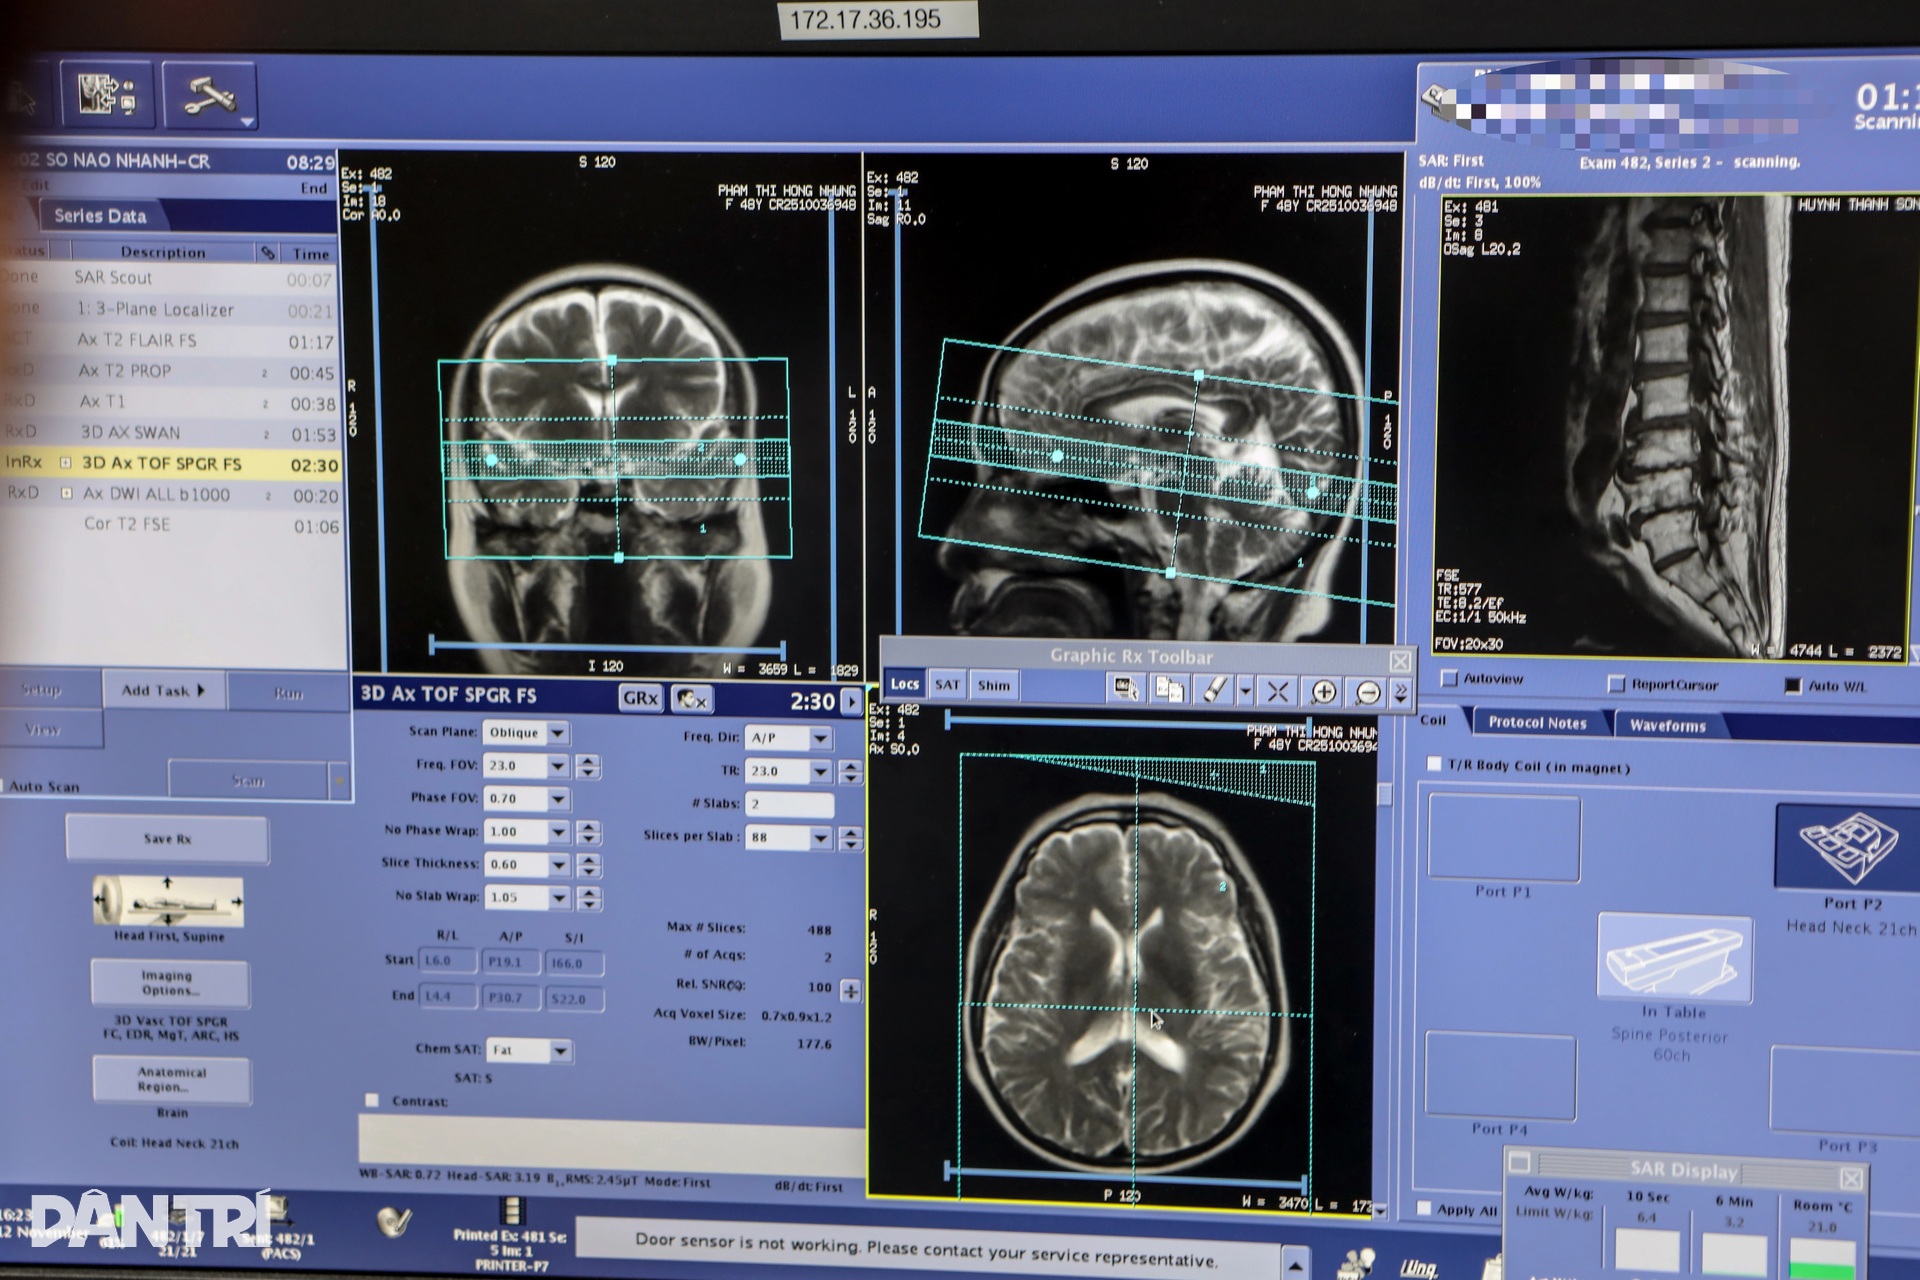

Bệnh viện Chợ Rẫy vừa chính thức đưa vào hoạt động hệ thống chụp cộng hưởng từ (MRI) 3.0 Tesla SIGNA Premier, đánh dấu bước tiến vượt bậc trong công nghệ chẩn đoán hình ảnh tại khu vực phía Nam. Đây là hệ thống MRI đầu tiên thuộc thế hệ tiên tiến nhất hiện nay được triển khai tại đây, với khả năng chụp nhanh gấp đôi so với các dòng máy trước.

Theo ông Bùi Văn Phẩm, Kỹ thuật y trưởng khoa Chẩn đoán hình ảnh, Bệnh viện Chợ Rẫy, công nghệ chụp nhanh của máy MRI 3.0 Tesla giúp rút ngắn đáng kể thời gian thực hiện, từ 15-20 phút xuống chỉ còn 7-10 phút. Điều này không chỉ giảm thời gian chờ đợi mà còn giúp bệnh nhân giảm bớt cảm giác lo lắng, mệt mỏi khi phải nằm yên trong thiết bị.

Điểm nổi bật của hệ thống này là việc tích hợp nền tảng trí tuệ nhân tạo (AI) toàn diện. Nền tảng AIR Recon DL sử dụng công nghệ học sâu để tái tạo hình ảnh, không chỉ giảm nhiễu mà còn tăng độ phân giải hình ảnh lên đến 60%, mang lại độ chính xác cao trong chẩn đoán.

Hệ thống này cũng hỗ trợ các ứng dụng chuyên sâu trong chẩn đoán thần kinh, với khả năng khảo sát chi tiết các bó sợi thần kinh, giúp phát hiện cả những tổn thương rất nhỏ, đánh giá chính xác các tổn thương do đột quỵ hoặc các bệnh lý thoái hóa thần kinh.

Hình ảnh từ máy MRI được truyền nhanh chóng đến máy tính của kỹ thuật viên và sau đó chuyển đến máy tính của bác sĩ qua hệ thống bệnh án điện tử.